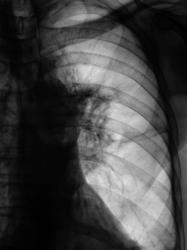

Начало 2008 года. При расшифровке цифровых флюорограмм пациент "взят на контроль", дообследован.

Конец 2008 г. При расшифровке цифровых влюорограмм пациент повторно взят на контроль и дообследован

Сегодня пациент прислан на рентгенологическое исследование органов грудной полости

Грустно и к сожалению довольно обычно, чаще всего пропускается s6 слева. Очень хочется знать, что подразумевается под "взят на контроль и дообследован"? Потому что изменения в левом корне, позволяющие заподозрить заболевание видны на первых снимках. Кроме того дообследуйте грудной отдел позвоночника - значительно снижена высота грудного позволка на уровне ателектаза.

Дообследование (первое) заключалось в рентгенографии в прямой и боковой проекциях, линейной томографии. Кстати, весьма хорошо "размазали" левый корень и направили в областной ОД. Кстати, тогда в грудных позвонках еще секундарных изменения не было.

В той, о которой я говорил - "Данных за онкологический процесс нет". Рекомендовано то - то и то - то и рентген-контроль через 3 месяца. Самое плохое, что и пациент успокоился, да и участковый терапевт (в конце года), с учетом появления субфебрилитета направил не на рентгенологическое исследование, а на флюорографию. Взяли на контроль, опять дообследовали, но уже в большем объёме, произвели и томографию позвоночника - на боковой рентгенограмме "визуализировалась порозность", ну а на томограммах ....